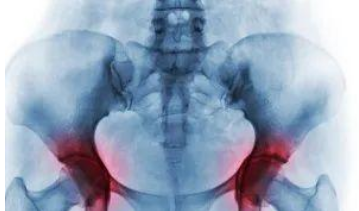

2急性发作的盆腔炎

急性盆腔炎患者前来就医时一般表现为下腹疼痛,伴有心率快、发热、阴道有大量脓性分泌物。病情严重者可能有高热、头痛、小腹胀痛、呕吐、腹泻等。

门诊医生首先要给患者进行抗生素抗感染治疗,然而,居高不下的体温会使抗感染治疗无效——如果感染控制不住,很有可能随时会发生感染中毒性休克、脓毒血症等严重并发症。就需要做一个腹腔镜探查手术,再进行下一步治疗。

需要注意的是,女性盆腔炎看似只是一个炎症,但一旦处理不好,除了危险重重以外,很多女性朋友得不到正确的治疗时,最终转变为慢性盆腔炎、慢性盆腔痛,于是它就成了一个令许多妇科医生都非常头疼的疾病了。